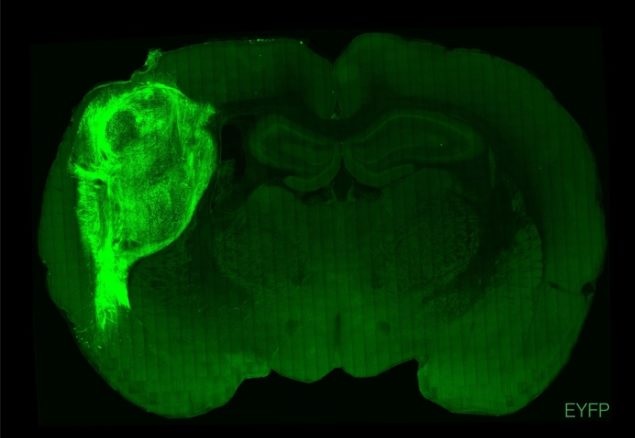

Самоорганизующиеся куски ткани человеческого мозга, выращенные в лаборатории, успешно пересадили в нервную систему новорожденных крыс, что является шагом на пути к поиску новых способов лечения нервно-психических расстройств.

Трехмерные органоиды, разработанные из стволовых клеток, напоминающие упрощенную модель коры головного мозга человека, соединены и интегрированы с окружающей тканью в коре головного мозга каждой крысы, образуя функциональную часть собственного мозга грызуна.

Человеческие кортикальные органоиды культивировали в чашке, а затем трансплантировали непосредственно в соматосенсорную кору (область мозга, ответственную за получение и обработку сенсорной информации) молодых крыс, которым было всего несколько дней. Затем этих грызунов оставили расти во взрослых особях еще на 140 дней (крысы полностью достигают половой зрелости между 6 и 12 неделями).

После поведенческих тестов крыс подвергли эвтаназии, а их мозг извлекли и препарировали, что позволило исследователям наблюдать интеграцию органоидов на клеточном уровне. Они обнаружили, что органоидные нейроны выросли намного больше, чем любые нейроны, выращенные в пробирке, проникая в мозг крыс и образуя сети с родными нейронами крыс.